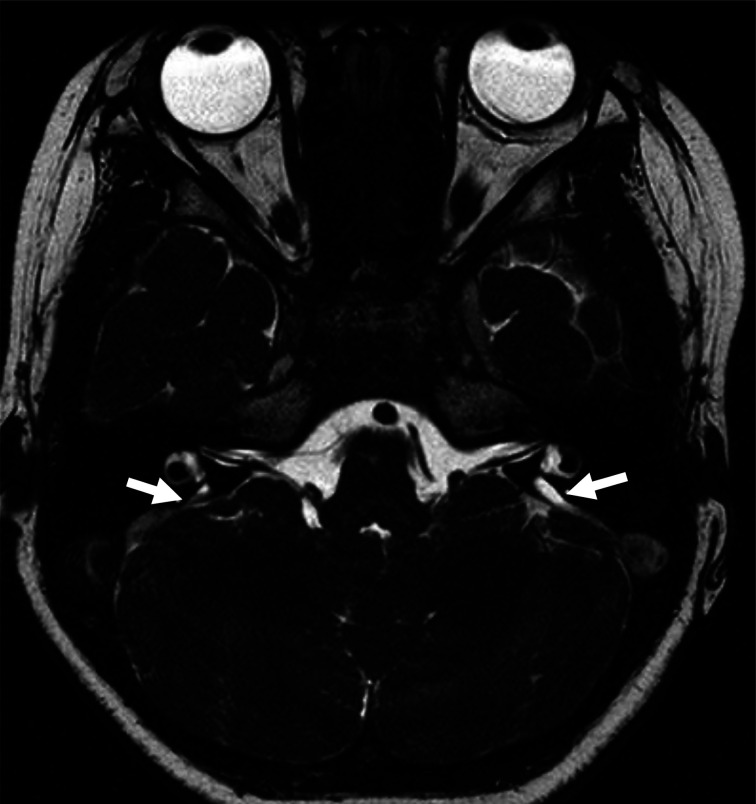

SLC26A4 可导致彭德综合征(Pendred Syndrome,PS)和非综合征性听力损失。PS是根据高氯酸盐排出试验异常、甲状腺肿和部分患者甲状腺功能减退来区分的。PS的甲状腺功能障碍的病理生理学与自身免疫性甲状腺疾病不同,它被认为是由碘的组织化缺陷引起的。一般认为,这两种疾病可能偶然同时存在,而SLC26A4可能在自身免疫性甲状腺疾病的病因中扮演重要角色。在此,我们描述了一例患有听力损失的女孩,她有两个致病的SLC26A4变体,并且甲状腺过氧化物酶(TPO)抗体检测呈阳性。她在 4 岁时被诊断出患有听力损失和前庭导水管扩大。耳聋基因筛查发现了两个致病性 SLC26A4 变体。由于 SLC26A4 变异可导致 PS,患者接受了全面的甲状腺检查。她的甲状腺属于轻度肿大的生理范围。虽然甲状腺功能检测结果正常,但患者的 TPO 抗体检测呈阳性。患者被诊断为 "疑似 PS "和 "疑似桥本氏甲状腺炎",这两种疾病都会增加甲减的发病风险。评估桥本氏甲状腺炎与 SLC26A4 变异体的并发症至关重要。

SLC26A4 causes Pendred syndrome (PS) and nonsyndromic hearing loss. PS is distinguished based on perchlorate discharge test abnormality, goiter, and hypothyroidism in some patients. The pathophysiology of thyroid dysfunction in PS differs from that of autoimmune thyroid disease, in that it is considered to be caused by an iodide organification defect. It is believed that both diseases may incidentally coexist, and that SLC26A4 may play an important role in the etiology of autoimmune thyroid disease. Herein, we describe a case of a girl with hearing loss who had two pathogenic SLC26A4 variants and tested positive for thyroid peroxidase (TPO) antibody. She was diagnosed with hearing loss and vestibular aqueduct enlargement at the age of 4 yr. Deafness gene screening revealed two pathogenic SLC26A4 variants. As SLC26A4 variants can cause PS, the patient underwent thorough thyroid examination. Her thyroid gland was within the physiological range of mild enlargement. Although thyroid function test results were normal, the patient tested positive for TPO antibody. The patient was diagnosed with "suspected PS" and "suspected Hashimoto's thyroiditis," both of which increase the risk of developing hypothyroidism. Evaluating the comorbidity of Hashimoto's thyroiditis with the SLC26A4 variant in terms of complications is critical.